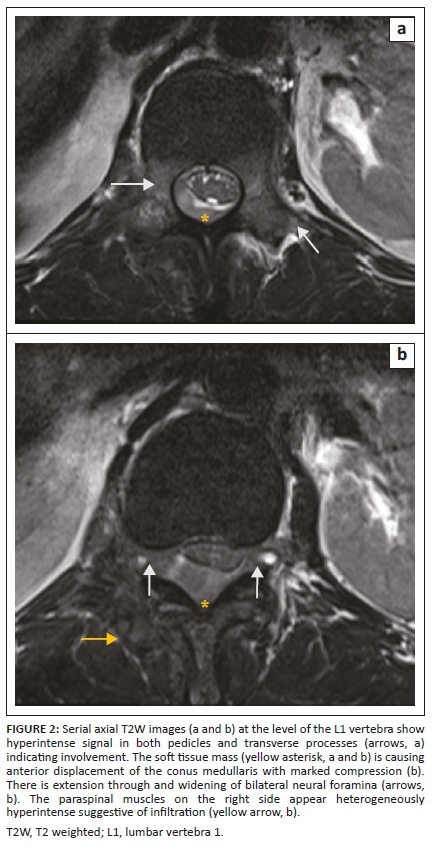

The MRI examination revealed altered signal intensity involving the bodies and posterior elements of the T12 vertebra and L1 vertebra which showed hypointense signal on T1 weighted (T1W) and hyperintense signal on T2W and short tau inversion recovery (STIR) sequences (Figures 1 and 2) with mild enhancement on post contrast images. On chemical shift imaging, the involved vertebral body did not show reduction in signal on opposed phase images (Figure 3). There was a homogeneously enhancing soft tissue mass in the posterior epidural space extending from the T12 to L2 vertebral levels appearing isointense on T1W and hyperintense on T2W and STIR images (Figures 2 and 4). The lesion caused narrowing of the spinal canal with marked compression of the conus medullaris and cauda equina nerve roots. There was associated widening of bilateral neural foramina (right > left) at the T12-L1 and L1-L2 levels, with infiltration of the soft tissue lesion into bilateral paraspinal muscles. A possibility of myeloid sarcoma was suggested given the clinical profile and imaging findings.

A precise and prompt diagnosis of chloroma is crucial as it allows the institution of definitive radiotherapy or adjuvant chemotherapy for local control of the disease, which helps in relieving cord compression and obviates any unnecessary surgery. Magnetic resonance imaging forms the cornerstone in the evaluation and diagnosis of spinal involvement in chloroma by aiding in spatial localisation (i.e. vertebral, epidural, intradural extramedullary and intramedullary), determining its extent and assessing the degree of cord compression, if present. At MRI, vertebral involvement in chloroma manifests as focal, multifocal or diffuse leukaemic infiltration of the vertebral marrow with low signal intensity on T1W, high signal intensity on T2W images and avid enhancement on post contrast images. Chemical shift imaging remains a useful entity when differentiating this condition from red marrow conversion. A propensity for ligamentous and subperiosteal involvement is also seen as a result of spread via the haversian canals.6 However, this non-specific appearance can be confused with marrow infiltrating disorders such as multiple myeloma and lymphoma; hence, a thorough clinical history of haematological disease is imperative in establishing the diagnosis.

Epidural involvement in chloroma can often occur in conjunction with vertebral body involvement. These often present as multiple masses which may be either contiguous or discrete, involving different vertebral levels. They usually show isointense and intermediate signal on T1W and T2W images respectively, with homogeneous post contrast enhancement.7,8 Central non-enhancing necrotic areas may be identified and diffusion restriction may be noted on diffusion weighted images. The lesions can cause effacement of the epidural fat with inward displacement of the dura mater and compression of the spinal cord with partial or complete obliteration of the cerebrospinal fluid (CSF) space. Frequent association with compressive myelopathy or neuronopathy, regardless of lesion location, is also seen. The combined intra-extraspinal form of chloroma, with a resultant 'dumb bell configuration', may simulate the appearance of a nerve sheath tumour on imaging. In such scenarios, absence of intense T2 hyperintensity without secondary bony changes (destruction or remodelling) favours chloroma.4